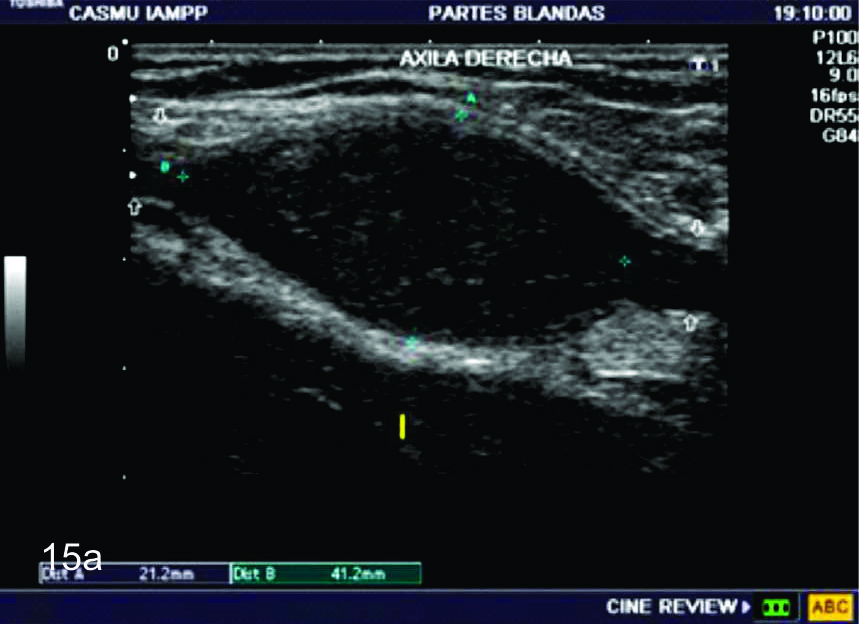

Figura 15

Tumor del nervio cubital a nivel del hueco axilar derecho.

A- SE observa un corte longitudinal del nervio cubital en donde se identifica una lesión sólida, expansiva, fusiforme (marcada entre calipers), la cual se encuentra en continuidad con el nervio cubital (flechas blancas abiertas). B- Corte transversal del mismo paciente en donde se identifica un área quística dentro del tumor, más frecuente en los schwanomas (flecha roja), Flecha amarillaarteria axilar. C- Con el empleo del Doppler de potencia se observa como el tumor se encuentra levemente vascularizado.